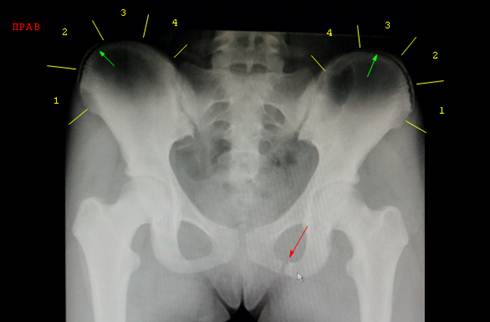

Снимок

таза девочки 15 лет, выполненный по поводу травмы. Хорошо визуализируются ядра

окостенения передних верхних остей и краёв крыльев подвздошных костей. Слева

ядро гребня дошло до третьего сегмента, справа до второго (зелёные стрелки).

Следовательно, признак Риссера равен трём.

Красной стрелкой обозначен перелом нижней ветви лобковой кости слева,

локализованный практически в зоне её слияния с ветвью седалищной кости (их

слияние происходит в возрасте 5 лет).